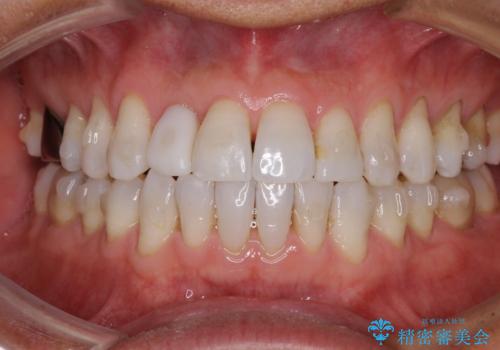

治療途中の前歯を治したい インビザライン矯正とオールセラミッククラウン

- 治療途中の前歯と上下前歯のデコボコ気にして来院された患者様です。

前歯のデコボコはインビザラインにより歯列を整え、その後に、前歯などをオーダーメイドタイプのオールセラミッククラウンにて補綴治療することとしました。

長時間のマウスピース装着に協力いただき、短期間で歯列をしっかりと改善することができました。

ホームホワイトニングを併用していただいたので、とても明るい口元に仕上がり、患者様には大変満足していただきました。